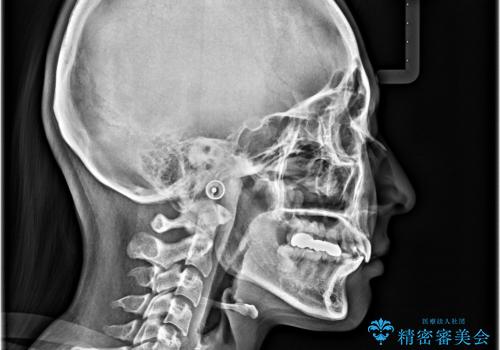

矯正治療後には、上顎欠損部をオールセラミックブリッジにて補綴治療を行うこととしました。

予想通りに治療は困難を極め、その上途中来院されない時期があったため、非常に長期間に及びましたが、周囲の方々が驚愕するほど口元の印象を改善することができました。